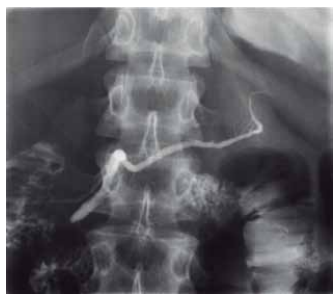

O exame radiológico contrastado com iodo, colangiopancreatografia retrógrada endoscópica, permite a visualização dos ductos biliares e pancreáticos. O ducto que encaminha uma secreção rica em bicarbonato de sódio, tripsina, quimotripsina, lipase, amilase e proteases, ao sistema digestório, é demonstrado pela radiografia a seguir:

Enunciado 4560246-1

(Arquivo pessoal; imagem usada com autorização)

A imagem refere-se ao ducto